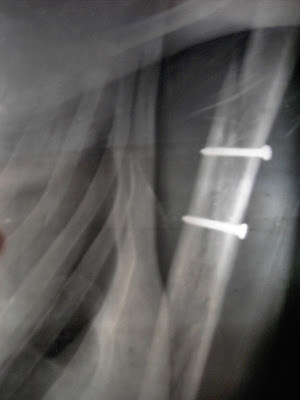

Como conto na história (Tenho um parafuso a menos? Desculpa! Tenho é 2 a mais)

Vim a saber que o meu braço, além dos parafusos, tinha também um músculo cortado. Estava difícil recuperar os movimentos, porque esteve engessado tanto tempo.